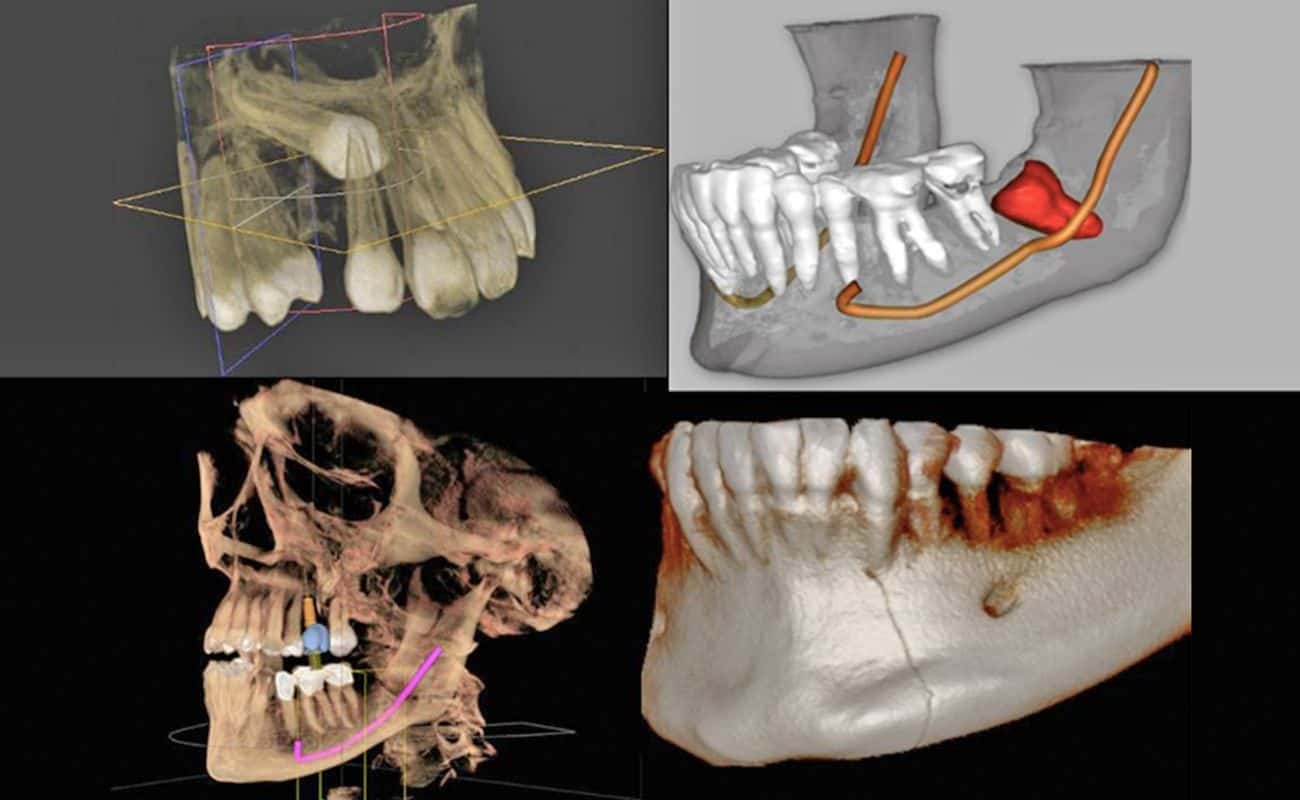

Cone Beam

El Cone beam o CBCT (Cone Beam Computed Tomography), llamado también tomografía volumétrica digital de haz cónico, es una técnica de imagen seccional en 3D en pleno auge. Permite el examen de tejidos calcificados, a saber, el hueso y los dientes.

En Cone Beam se les solicita a los pacientes que necesitan o desean colocarse implantes dentales. El estudio es básico para que el peridoncista pueda establecer un plan de tratamiento y una guía para la cirugía.